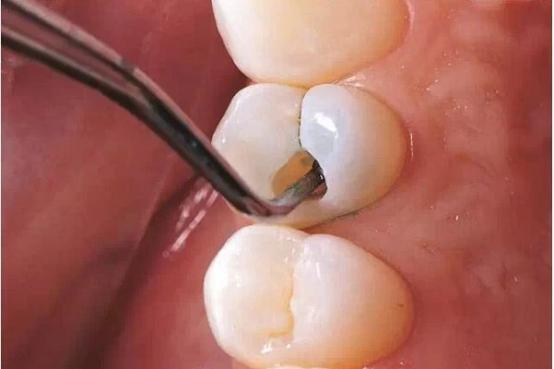

1、龋齿充填以后发酸,一般发生于中度或深度的龋坏。

由于龋齿已经达到了牙本质层或者是牙本质的深层,所以在用牙钻去龋的时候是会造成牙齿酸痛症状的。这种症状有可能是由于牙钻机械刺激造成的,也有可能是由于喷的冷水造成的,而且还是由于牙齿本身,牙本质敏感造成的。如果这种敏感不严重,观察处理即可,后期它也可能会逐渐恢复到正常状态。但如果反而加重,则应该及时就医,让医生重新检查、处理。

2、补牙充填后龋齿发酸还可能是另外一个原因,牙齿上充填的物体可能存在咬合的高点。

一般补过牙后会让患者咬一张蓝色的纸,有高点的蓝色的点的地方医生会把它磨掉。但可能患者咬的位置不是很正确,或者没有细心,导致医生不能按照正确的判断来把高点磨掉。